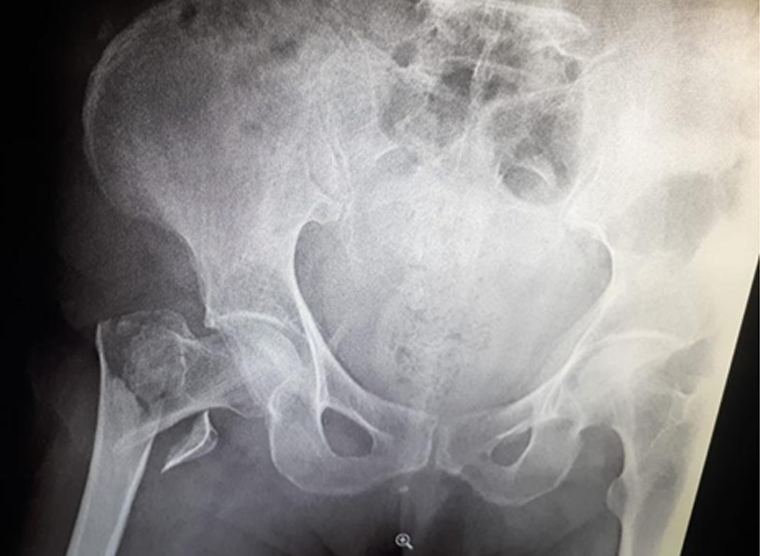

We will ask to get a x-ray of the hip joint to confirm the fracture. Sometime We may ask for CT scan or MRI scan when x-ray is not sufficient to diagnose.